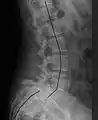

| X-ray of the lateral lumbar spine with a grade III anterolisthesis at the L5-S1 level | |

- Grade III: 50–75%